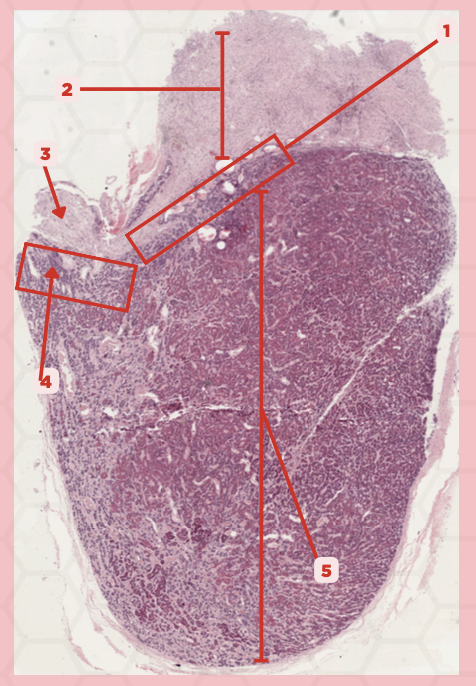

Pituitary

Identify the specimen.

Anterior Lobe

Identify the structure labeled as 1.

Posterior Lobe

Identify the structure labeled as 2.

Intermediate Lobe

Identify the structure labeled as 3.

Pars Tuberalis

Identify the structure labeled as 4.

Pituitary Stalk

Identify the structure labeled as 5.